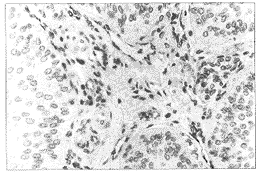

PCNA为颗粒型阳性,定位于细胞核,呈黄褐色(图1),每张切片选取10个不同视野用网 格测微尺记数100个网格内肿瘤细胞数及阳性核细胞数,计算阳性核细胞数占总的肿瘤细胞 数的百分比,再取10个视野的平均值作为该患者膀胱移行细胞癌的PCNA值。VWF:Ag以血管内 皮细胞染成棕黄色为阳性(图2),单个的内皮细胞着色也判断为阳性。用OLYMPUS显微镜在 200倍视野下对每例膀胱移行细胞癌的VWF:Ag染色切片选取10个血管数目最多的视野计数其 血管数,计算其平均数。

图2 VWF:Ag在膀胱移行细胞癌组织中的表达:

可见肿瘤间质血管内皮细胞染成棕黄色LSAB法×200